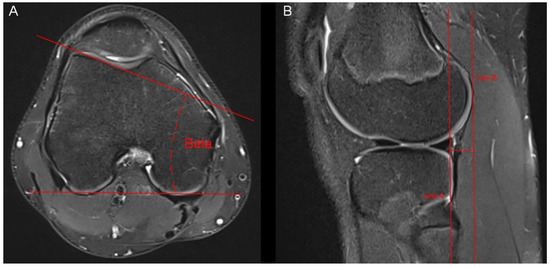

Figure 1. Measurement of the Insall–Salvati ratio and the tibial tubercle deviation. (A) Insall–Salvati ratio: Measurement of the largest superiorinferior diameter of the patella (A) in sagittal MR-images in which the tibial insertion of the patellar tendon can be identified. Measurement of the patellar tendon length (B). Insall–Salvati ratio = B/A. (B,C) Tibial tubercle deviation: We drew a line (line X) that connected the posterior aspect of both femur condyles in the MR-image of the nearest subchondral spot of the femoral trochlea. After that, we drew a perpendicular line to line X (line Z), which passed the nearest subchondral spot of the femoral trochlea (P). We scrolled line Z to the axial level of the tibial insertion of the patellar tendon. The tibial tubercle deviation represents the distance between line Z and the midpoint of the insertion of the patellar tendon at the tibial tubercle (T).